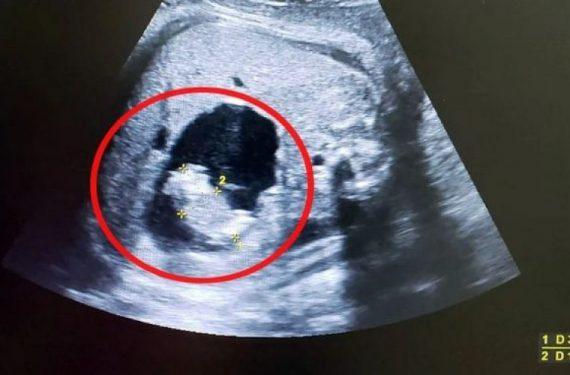

Αρχικά οι γιατροί νόμισαν ότι το νεογέννητο μωράκι είχε μια κύστη, ωστόσο διαπιστώθηκε ότι επρόκειτο για τη δίδυμη αδερφή της, την οποία είχε «απορροφήσει» στα πρώτα στάδια της εγκυμοσύνης.

Μια γυναίκα από την Μπαρανκίγια της Κολομβίας έφερε στον κόσμο ένα κοριτσάκι, στην κοιλιά του οποίου οι γιατροί διαπίστωσαν ότι υπήρχε το μικροσκοπικό σώμα της δίδυμης αδερφής της, το οποίο ήταν ακόμα υπό ανάπτυξη! Το φαινόμενο αυτό, που αποκαλείται επιστημονικά «fetus in fetu» (έμβρυο μέσα σε έμβρυο) είναι εξαιρετικά σπάνιο αλλά έχει ξανασυναντηθεί στο παρελθόν. Διαβάστε περισσότερα ΕΔΩ